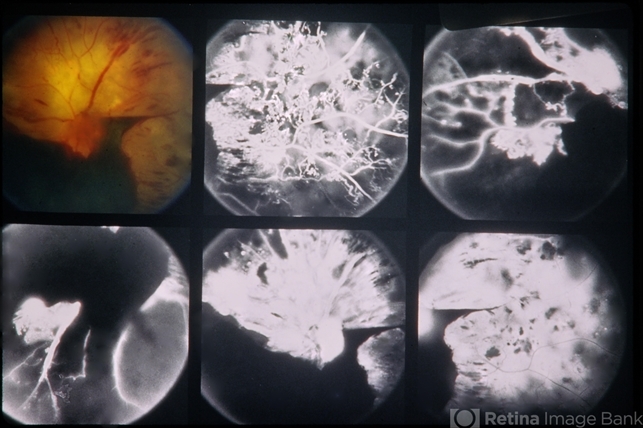

- 33-year-old white male. 20/200 and 20/200. Proliferative diabetic retinopathy.